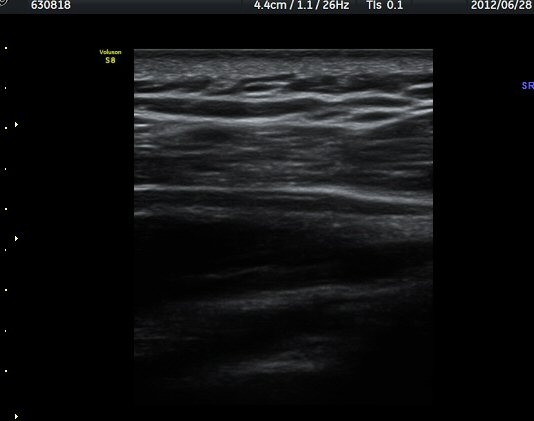

ÁÖ»ç¹Ù´Ã ÈíÀÎ(µ¿¿µ»ó Âü°í) 4ÀÏ ÈÄ °üÂûÇÑ ¼Ò°ß¿¡¼­´Â ³¶Á¾ÀÇ Å©±â °¨¼Ò°¡ ¶Ñ·ÈÇÏÁö ¾Ê´Ù(±×¸² 5, 6).